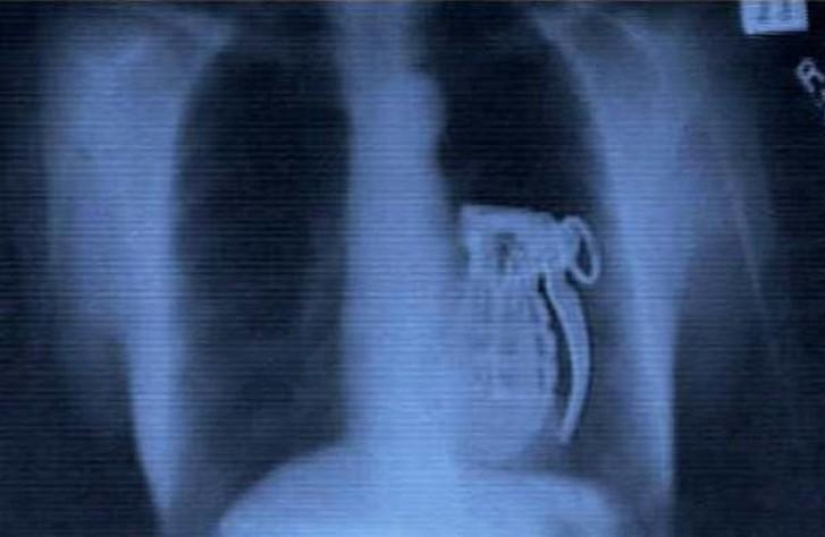

14. Granada.